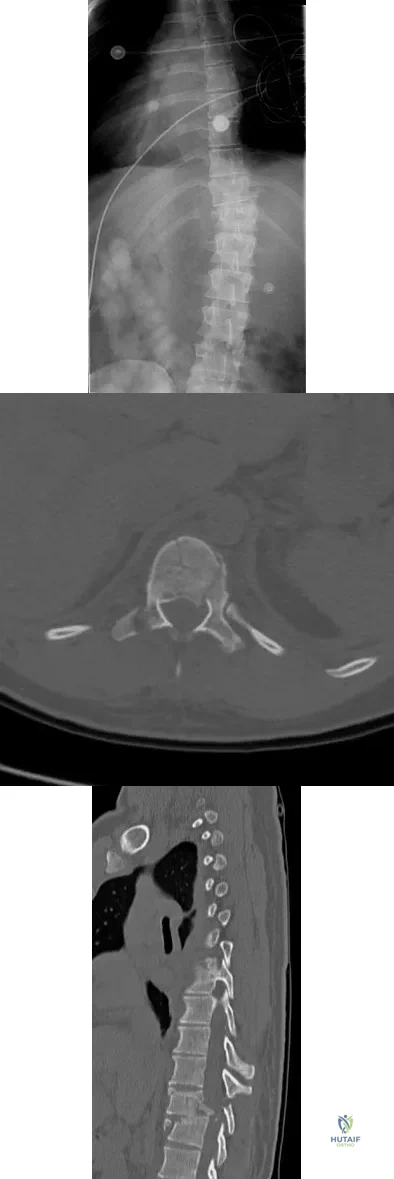

Question 80

A 23-year-old man is involved in a motor vehicle accident. An AP radiograph is shown in Figure 29a, and axial and sagittal CT scans are shown in Figures 29b and 29c. Neurologic examination shows 1/5 strength of his quadriceps and iliopsoas on the right, with 1/5 quadriceps function on the left. Definitive treatment of his injury should consist of

Explanation